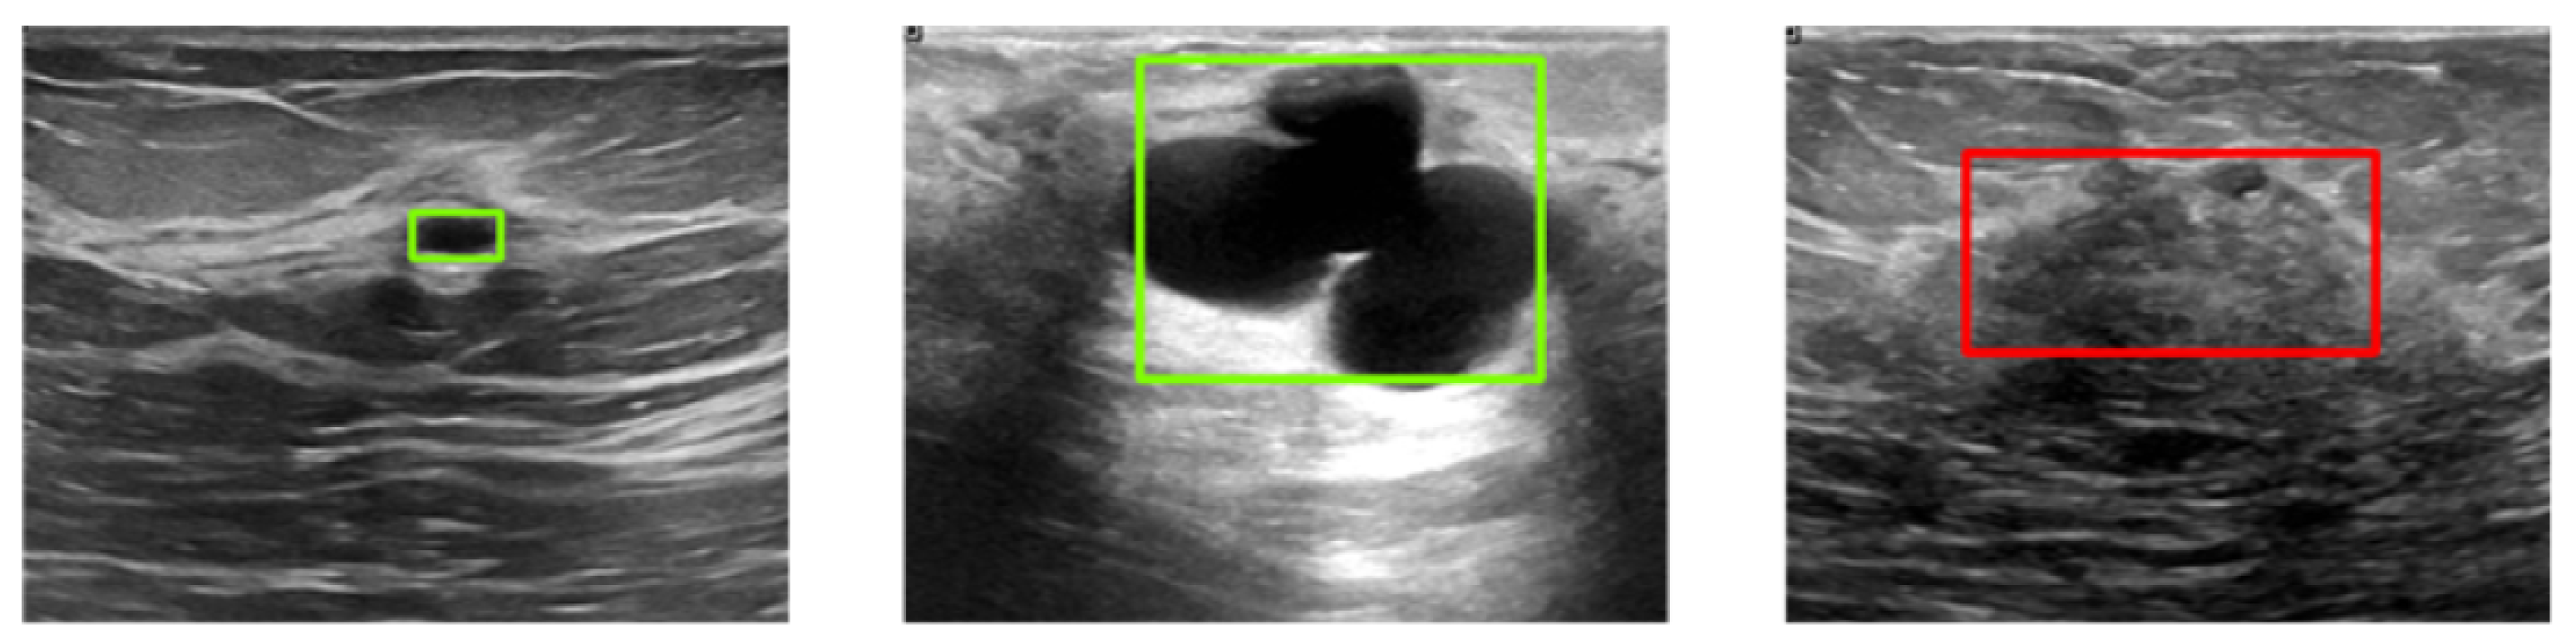

Figure 6 illustrates three example images with ground-truth annotations. Malignant tumors generally exhibit more irregular shapes and are more likely to be confused with normal tissue compared to benign tumors.

Figure 6.

Sample images from the BUSI dataset with ground-truth bounding boxes. Benign and malignant tumors are annotated with green and red boxes, respectively.